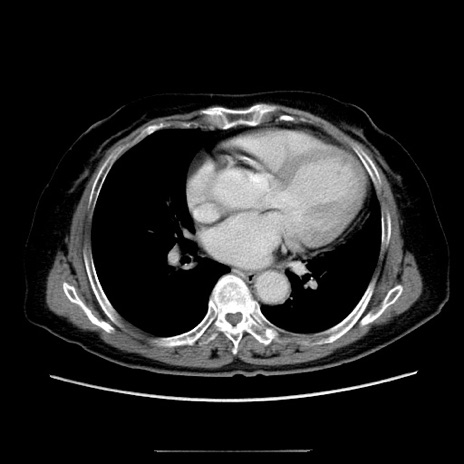

症例5(横断像)

【症例】70歳代女性

【主訴】お腹が張る

【現病歴】1週間くらい前から腹部膨満の自覚あり。昨日夜から増悪したため、本日救急外来受診。

【身体所見】意識清明、BT 36.5℃、BP 165/106mmHg、HR 80bpm、SpO2 98%、腹部:膨満、軟、自発痛・圧痛なし、触診にて不快感あり、腸蠕動音:減弱

【データ】WBC 12600、CRP 1.04